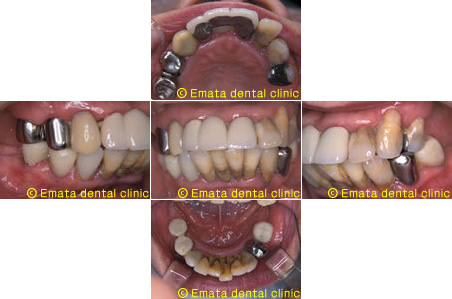

歯周再生・歯列補正・審美補綴まで一口腔単位で整えた包括治療

歯周再生療法 歯周矯正治療 ジルコニアセラミック治療

Before

After

| 主訴 | 歯がぐらぐらする。歯周病を治したい。 |

|---|---|

| 治療期間・回数 | 約2年・約15回 |

| 費用 | 2,300,000円 |

| デメリット・注意点 | 詰め物・被せ物の調整が難しく、割れた場合は再治療が必要。 |